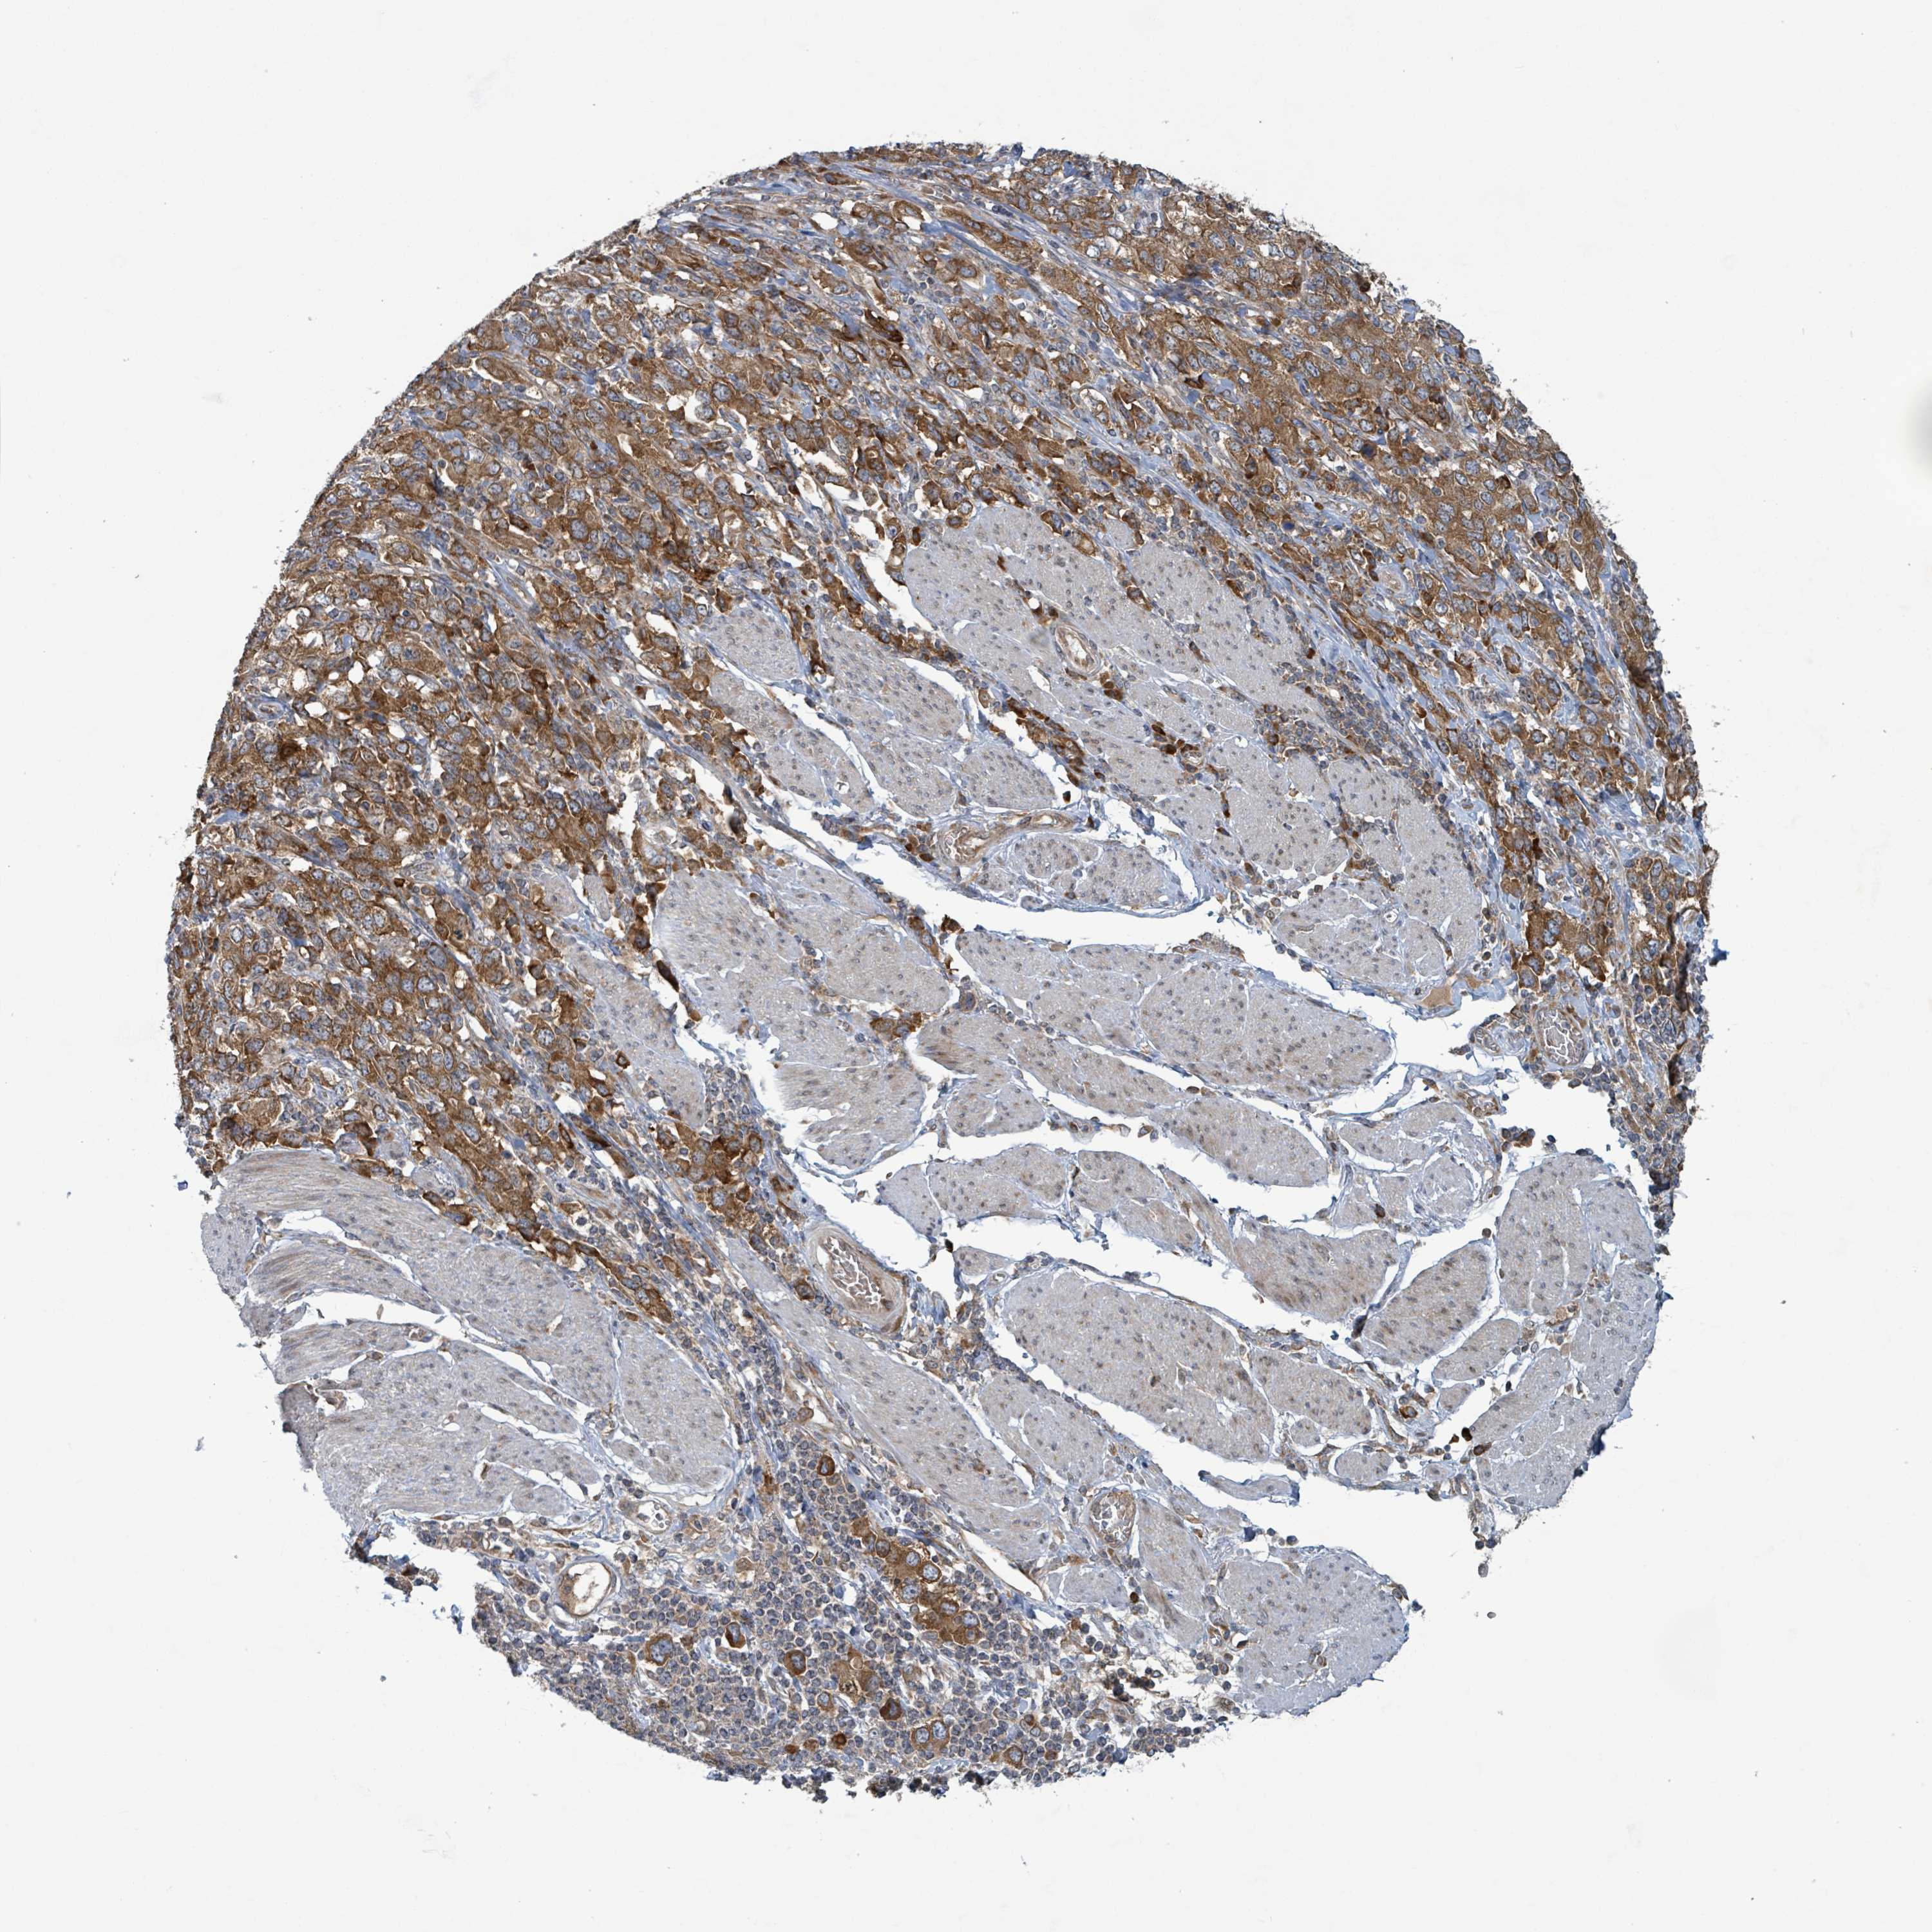

STOMACH CANCER - Protein expressioni

A mouse-over function shows sample information and annotation data. Click on an image to view it in a full screen mode. Samples can be filtered based on level of antibody staining by selecting one or several of the following categories: high, medium, low and not detected. The assay and annotation is described here.

Antibody stainingi

Antibody staining in the annotated cell types in the current human tissue is reported as not detected, low, medium, or high, based on conventional immunohistochemistry profiling in selected tissues. This score is based on the combination of the staining intensity and fraction of stained cells.

Each image is clickable and will lead to virtual microscopy that enables deeper exploration of all samples and also displays staining intensity scores, fraction scores and subcellular localization as well as patient and tissue information for each sample.

Antibody HPA051439

Antibody CAB019995

Adenocarcinoma, NOS